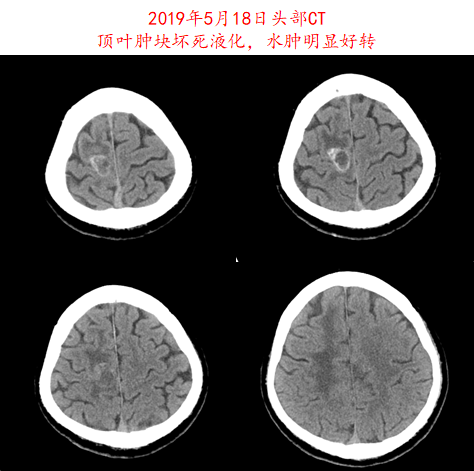

2019年4月16日开始给予信迪利单抗(200mg,q3w)+阿帕替尼(250mg,qd)治疗,治疗1周期后,患者症状明显改善,2周期后复查CT,疗效评价为部分缓解(PR;图3-4)。治疗期间患者出现1-2级皮疹,未观察到其他副作用。

image004.png

图3.患者2019年5月18日头部CT影像资料

image005.png

image006.png

图4.患者2019年5月18日胸部CT影像资料